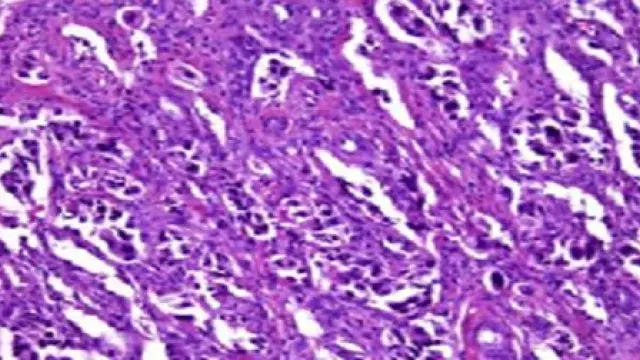

La investigación 'Epigenetic profiling to classify cup: a multicentre, retrospective analysis', publicada en la revista 'Lancet Oncology', fue realizada a partir del estudio de marcadores de metilación del ADN de 38 tipos de tumor y sus correspondientes metástasis con un banco de 10.500 muestras, con lo que se convierte en el estudio con mayor número de casos que se ha desarrollado en la literatura médica en este campo.

El resultado del test proporciona una información diagnóstica complementaria a otras pruebas -anatomía patológica, diagnóstico por la imagen, entre otros- realizadas con técnicas convencionales que permiten diagnosticar únicamente el 25% del cáncer, mientras que la herramienta desarrollada alcanza el 87% del diagnóstico.